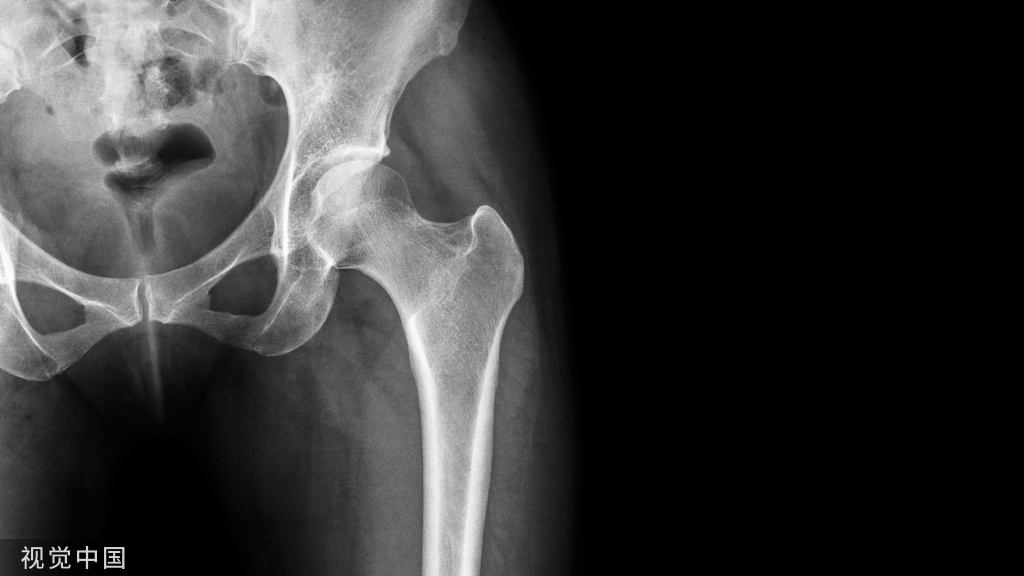

早在1879年,来自法国的DR.Segond发现,下肢过度的内翻加内旋暴力导致的胫骨平台前外侧撕脱骨折,常伴有前交叉韧带、内外侧半月板的损伤。这也就是我们现在经常讲到的Segond骨折👇。